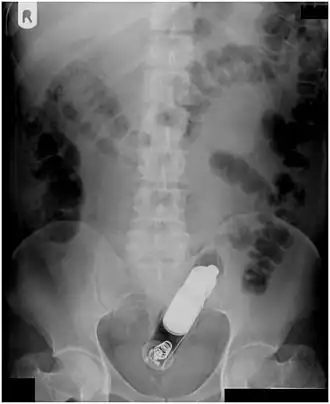

Vibrator stuck in the rectum can be seen on this abdominal X-ray. -